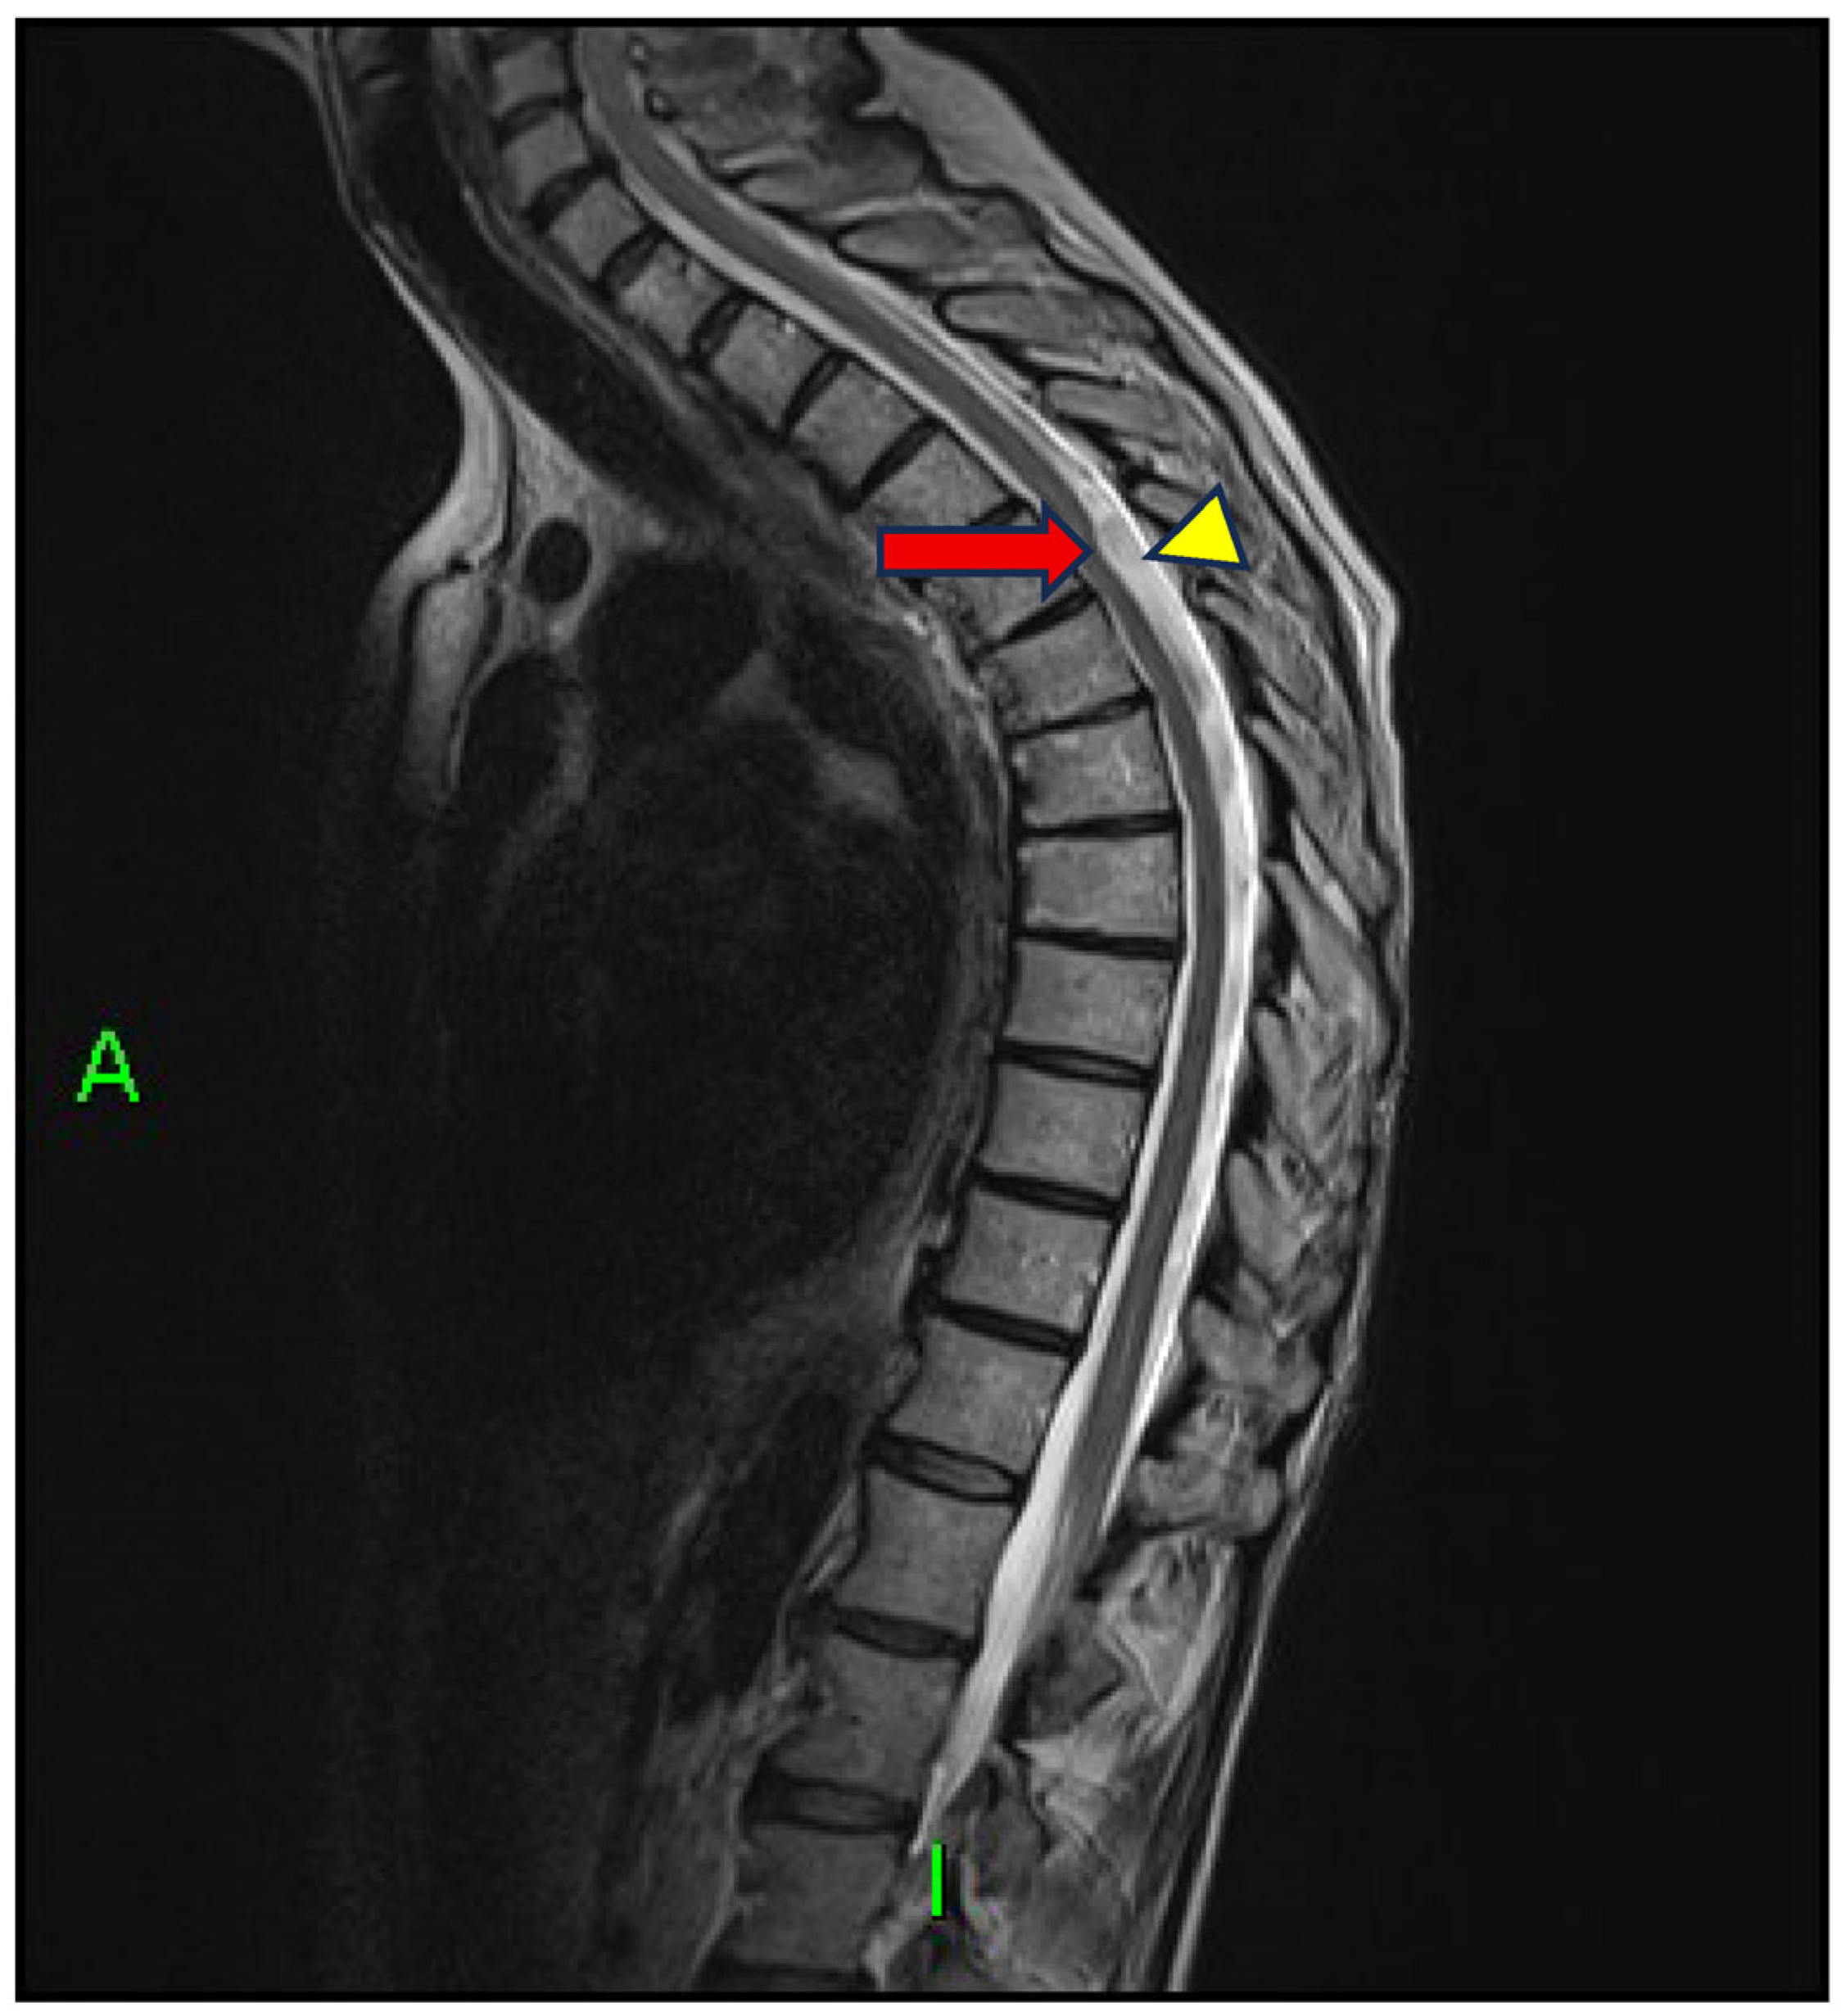

- Reardon, M.A.; Raghavan, P.; Carpenter-Bailey, K.; Mukherjee, S.; Smith, J.S.; Matsumoto, J.A.; Yen, C.P.; Shaffrey, M.E.; Lee, R.R.; Shaffrey, C.I.; et al. Dorsal thoracic arachnoid web and the “scalpel sign”: A distinct clinical-radiologic entity. AJNR Am. J. Neuroradiol. 2013, 34, 1104–1110. [Google Scholar] [CrossRef] [PubMed]

- Arora, V.; Verma, H.; Kamal, R.; Lone, N.A. Dorsal arachnoid web: The ‘scalpel’ sign—A case report and differential diagnosis. Egypt. J. Radiol. Nucl. Med. 2022, 53, 163. [Google Scholar] [CrossRef]

- Ruschel, L.G.; Agnoletto, G.J.; Aurich, L.A.; Vosgerau, R.P. Dorsal arachnoid web and scalpel sign: A diagnostic imaging entity. Turk. Neurosurg. 2018, 28, 689–690. [Google Scholar] [CrossRef]

- Brasil, P.; Pereira, L.; Távora, D.; Camara, A.; Filho, C.M.; Coimbra, P. Imaging findings in dorsal thoracic arachnoid web and the differential diagnosis of “Scalpel Sign”. Neurographics 2020, 10, 96–102. [Google Scholar] [CrossRef]

- Mukherjee, S.; Reardon, M.A.; Raghavan, P. Dorsal thoracic arachnoid web: Another intradural entity with ventral cord displacement. RadioGraphics 2015, 35, 297–298. [Google Scholar] [CrossRef] [PubMed]